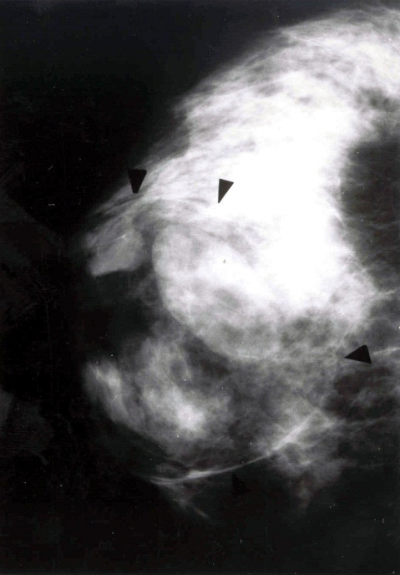

בממוגרפיה ניתן לראות גוש הסמיך יותר מסביבתו, שגבולותיו חדים ומופרדים מרקמת השד. קשה להבדיל גוש זה מגוש סולידי (תצלום 12.12).

רוב הפיברואדנומות מגיעות לגודל מסוים, מתייצבות ולא משתנות יותר מבחינת הגודל. רק בקבוצה קטנה יחסית תהיה נסיגה בגודל. בהריון לעתים הפיברואדנומות גדלות די מהר. בחלק מהחולות עלול להתפתח אוטם בפיברואדנומה הגורם להגדלה פתאומית של הגוש. במתבגרות ניתן למצוא את ה-Juvenile fibroadenoma או Giants fibroadenoma of the adolescence המתאפיינת בצמיחה מהירה של השד עם גודש ורידי עד התכייבות העור. השאת תלויה באסטרוגן ולכן היא משתנה בזמן המחזור וגורמת לא-סימטריה ניכרת של השדיים. בממוגרפיה ניתן לראות גוש סולידי מוגבל היטב בשד (תצלום 18.12), או גוש מסויד (תצלום 19.12). לעתים ניתן לראות גוש גדול, די שקוף רנטגנית, והוא מתאים להמרטומה של השד (תצלום 20.12).